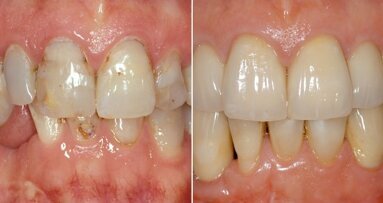

Fig. 13: Implant crowns in situ.

Once the implants are placed in situ and fully integrated, we then have a choice of conventional wet impression techniques versus digital intra-oral scanning. For the majority of cases, intra-oral scanning is extremely predictable and reliable—more so than conventional techniques—with milled (and lately printed) models having excellent properties and less accumulation of processing errors. However, deeply placed implants relative to adjacent teeth with deep contact points are very difficult to scan and pick up. Straumann tissue level implants offer a very straightforward restorative platform to scan from.